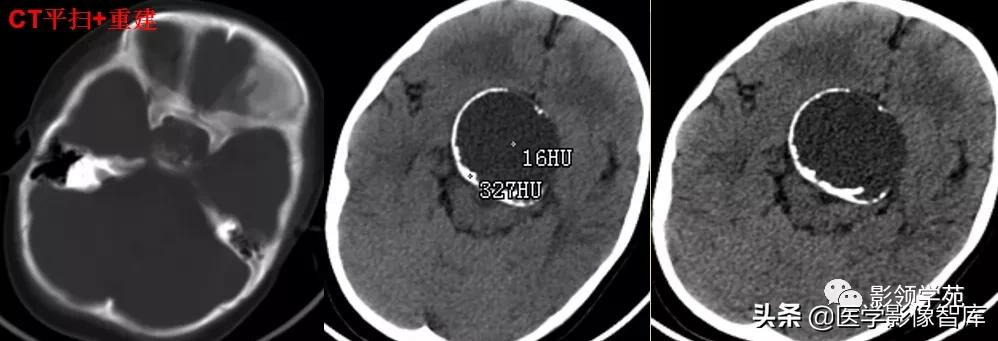

1、无血栓者:CT平扫呈稍高密度影,增强扫描呈明显均匀强化。

2、部分血栓者:CT增强扫描,中心和囊壁明显强化--靶征。

3、完全血栓者:CT平扫呈等密度影,增强时仅囊壁强化。

女 72岁,发现糖尿病3年余

鞍上区见一团块状稍高密度影,边界尚清,密度均匀。

病灶明显强化(瘤内血栓未强化),边界清楚,与右侧颈内动脉海绵段分界不清。垂体大小、形态未见异常。